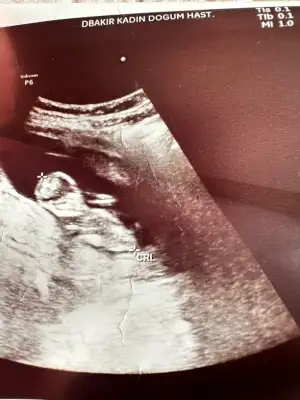

Merhaba kızlar 12 haftalık olduk cinsiyet ile ilgili içinizden ne geçiyor

Eklentiler

• IMG_2714.webp

IMG_2714.webp

57,4 KB · Görüntüleme: 53